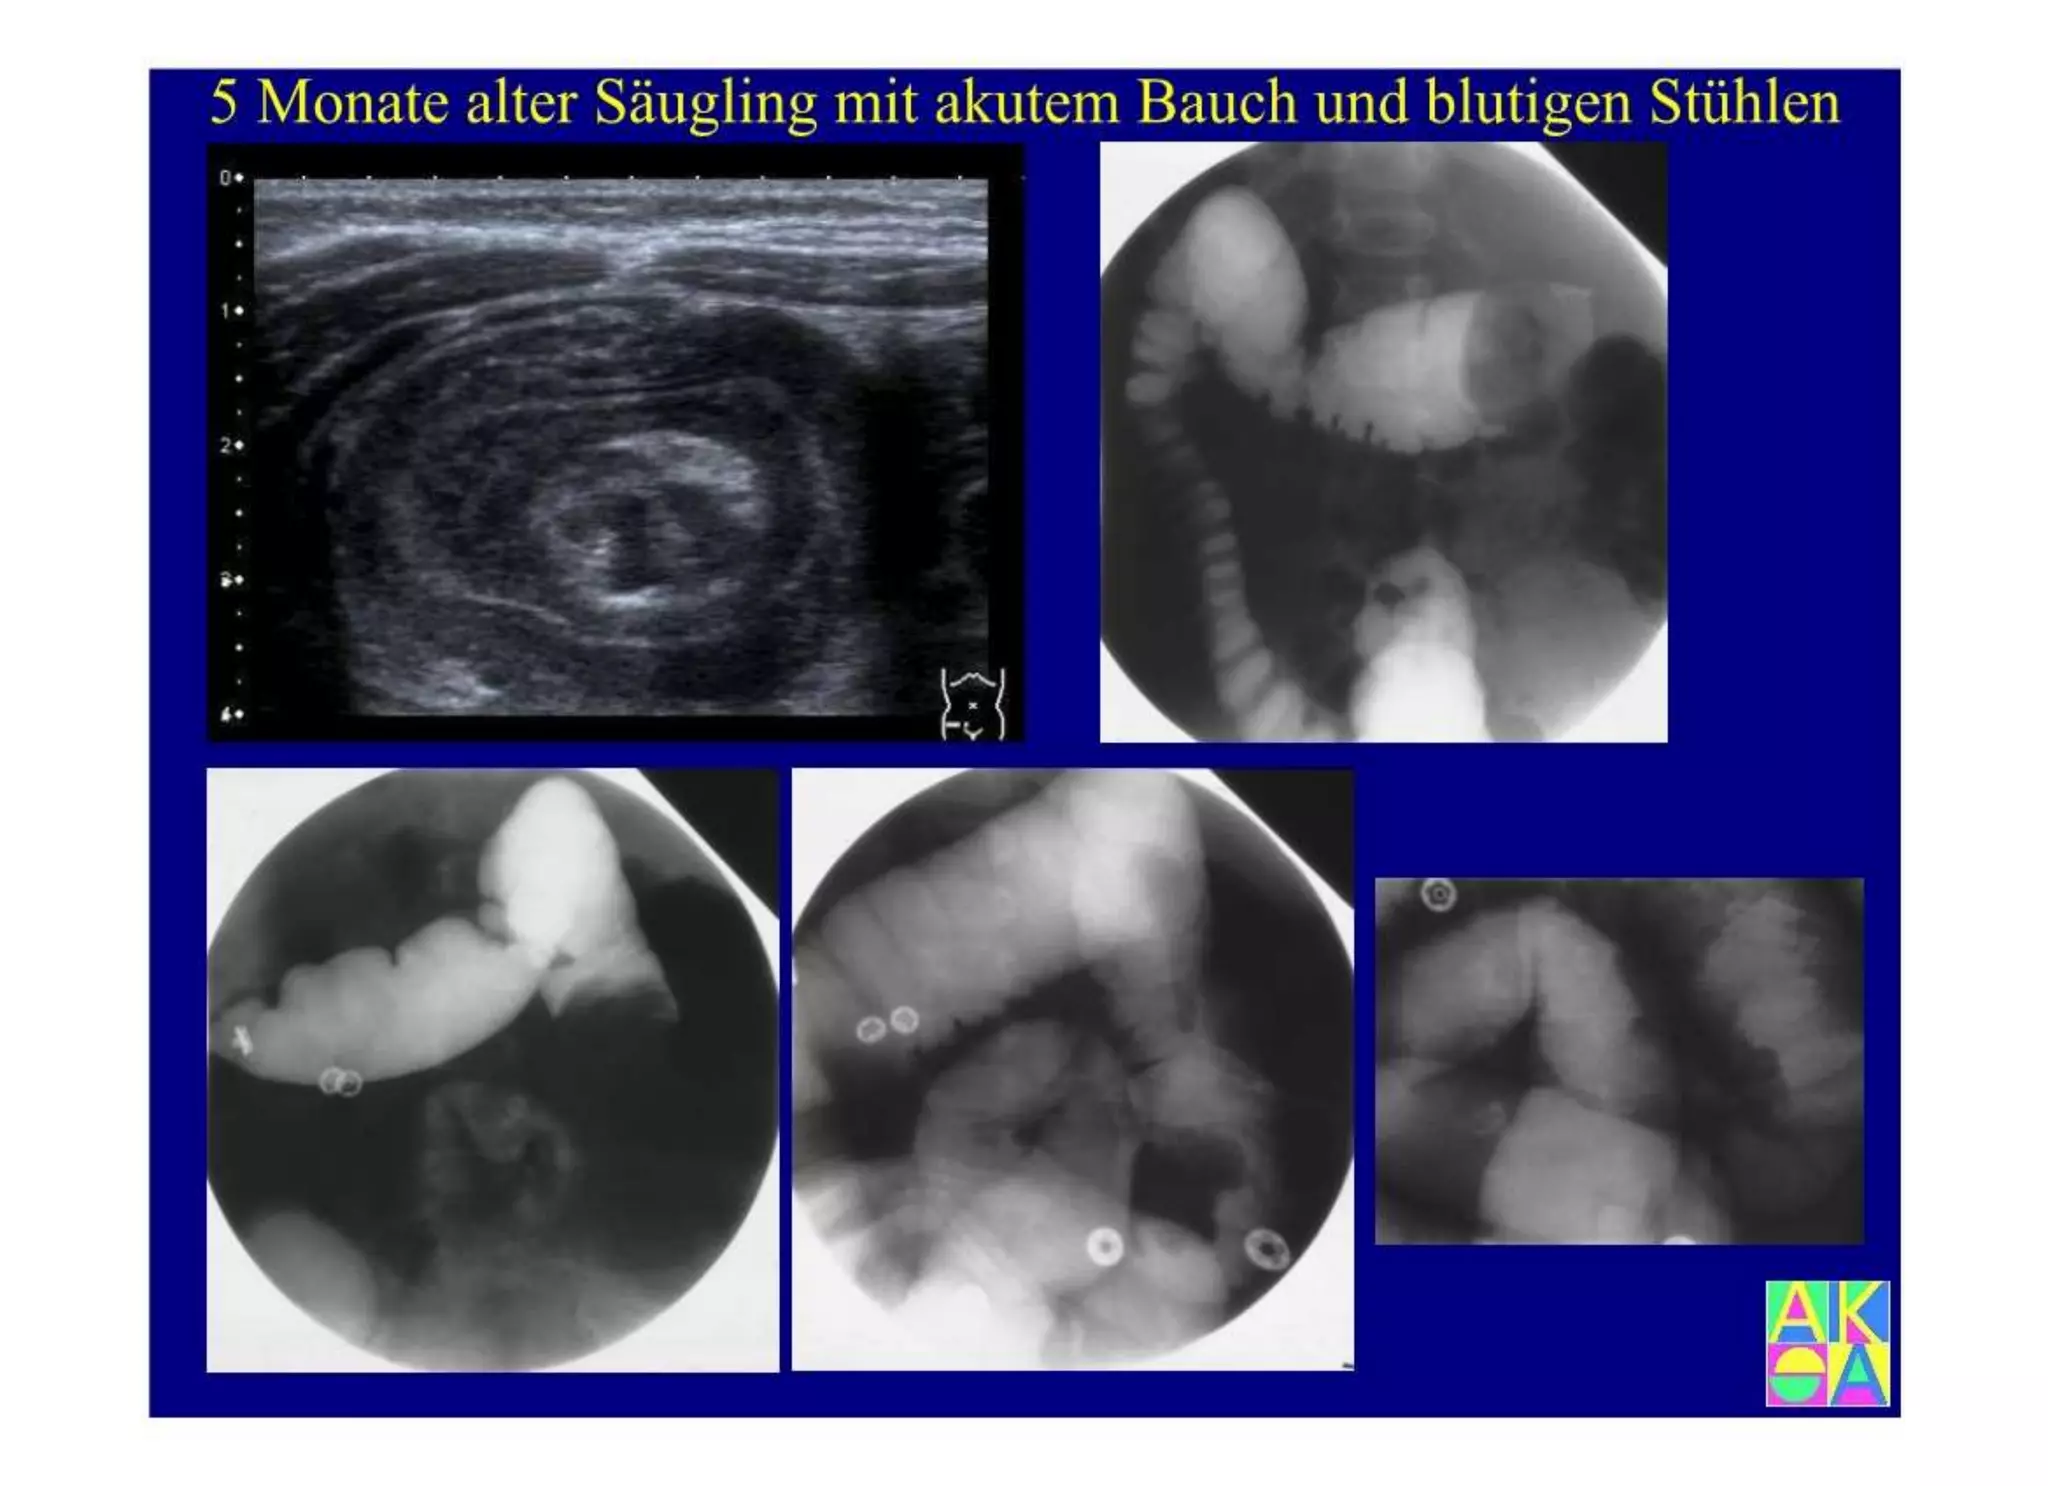

Chronische Enteropathie und Ileus, Dünndarm und Dickdarmdiagnostik, Mechanischer und paralytischer Ileus, Eingeklemmte Darmabschnitte, aufgereihter Bridenileus, und dazu Dickdarmileus, eingeklemmte Hernien, Weitergabeskript